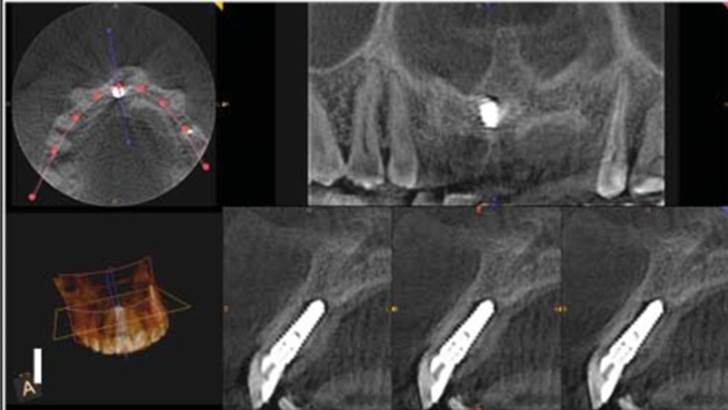

Clinical case: Bone growth in deepest thread of 8.0mm AnyRidge fixture

- Courtesy of Dr. Kwang Bum Park -

Clinical case: Bone filling into the bottom of deepest thread at 8.0mm AnyRidge fixture

Keywords

AnyRidge, Knifethread ,extraction socket, ,initial stability ,Allograft, ,osseointegratio ,Dr. Kwang Bum Park, , Mandibular, Single replacement, AnyRidge, Mega-oss,

Products used

Implant system-AnyRidge, Regeneration-Mega-Oss